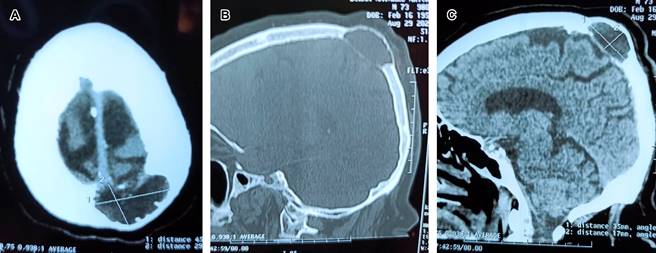

Figura 1: Imágenes tomográficas de cráneo. A) Corte axial superficial que muestra quiste leptomeníngeo de 8 cm de diámetro por 4 cm de profundidad. B y C) Cortes sagitales, se observa adelgazamiento de ambas Tablas óseas, siendo más importante el estrechamiento de la Tabla interna, con comunicación de leptomeninges al diploe.

El quiste leptomeníngeo (QL) es una complicación de la fractura craneal evolutiva, comúnmente conocida como “growing fracture”. Ocurre en la población pediátrica y son pocos los casos publicados en adultos, como en el presente reporte de un paciente masculino asintomático de 73 años, que en los últimos cinco años notó crecimiento óseo en región occipital con dimensiones 10 × 8 cm. La tomografía mostró QL (Figura 1). Se realizó una craneotomía con evacuación del quiste y reconstrucción con duramadre suturable y craneoplastia autóloga (Figura 2). Los QL se caracterizan por un crecimiento progresivo de la fractura, con un aumento de la dehiscencia en los bordes, lo que puede llegar a provocar deformidades. El defecto dural subyacente a la fractura y la fuerza mecánica de la pulsación cerebral provocan la herniación de la leptomeninge a través del defecto, ocasionando el QL. Su prevalencia es de 1.2% en niños menores de tres años. Suelen detectarse en los tres primeros años tras el traumatismo, pueden pasar desapercibidos durante años. El QL en adultos es una situación atípica muy poco descrita en la literatura, siendo el tratamiento quirúrgico el realizado en la mayoría de los casos.